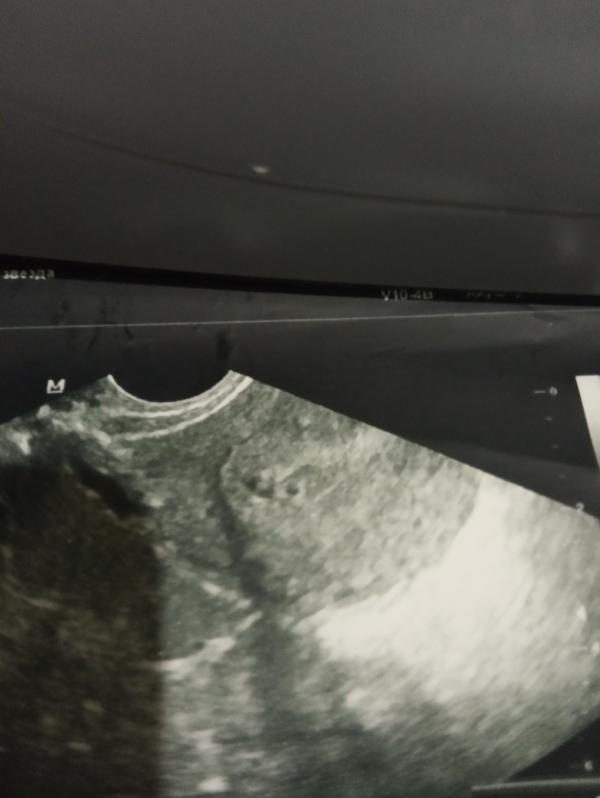

Девочки ну это пзд просто !!!!! У меня нет слов !!!! Была на УЗИ в авеню, на 40лет победы который, короче он когда смотрел ребенка видел, потом отсылал в вац ап мое УЗИ всем , звонил каким то бабам и просил посмотреть ! На мои вопросы не отвечал , говорил жди ! Потом после звонка какой то Бэлочки сказал ,что я не беременна жди месячных, на вопрос о ХГЧ промолчал говорит сдай через дней 10 посмотри , если месячные не пойдут то может что то все таки есть там !!!!!!!! Я так орала и ругалась там , г...